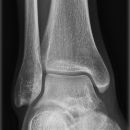

Sprunggelenk

Sprunggelenk a.p.

Freier Einblick in den kompletten Gelenkspalt? (Aufnahme in 15-20° Innenrotation, beide Malleolen in gleicher Tischplattenentfernung!) -> Kontur der Incisura fibularis tibiae und laterale Talusrollenkontur in einer Fluchtlinie?

Beurteilungskriterien

• Weite (lateral 4-5mm, medial 3-4mm) und Kongruenz des Gelenkspalts

• Syndesmosenspalt < 5mm

• Fluchtlinie von Incisura fibularis und lateraler Talusrollenkontur -> Versetzung weist auf (osteo-)ligamentäre Verletzung hin!

• tibiofibulare Gelenkkontur

• Weichteilschwellung (v.a. ventral des Gelenkspaltes in der seitlichen Aufnahme und um den lateralen Malleolus in der ap.-Projektion)